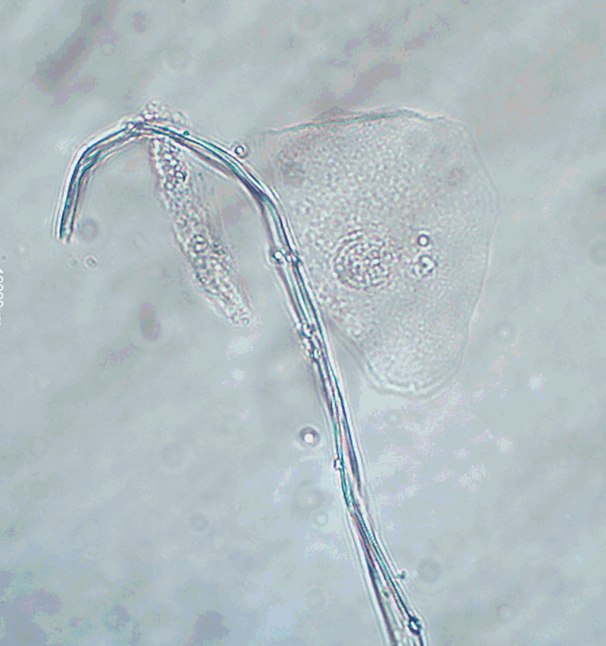

Sperm

knowt flashcard image

Typically insignificant unless found in a patient who is a minor